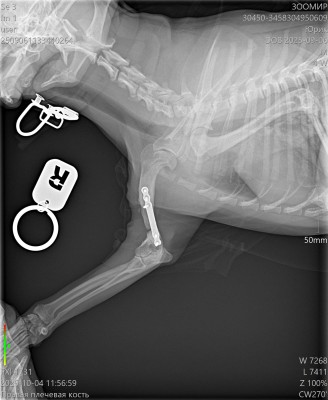

Сделали контрольный рентген - пока мозоли не видно:((((

Лапой на ровном немного пользуется. Но это за счет пластины.

Рентген

Юрик съездил сегодня на контрольный рентген.

Мозоль ОБРАЗОВАЛАСЬ. По центру она еще не очень плотная, но кость срослась.

Как Ольга паразита не оберегала, но на рентгене оказалась чуть погнутая пластина и один сломанный винт.

Снимать ничего не будем из конструкции, если не начнет отторгаться или двигаться.

2 рентгена и осмотр АН обошлись в 2600₽ ( это стоимось 2 снимков).

Юрик. Взгляд изнутри